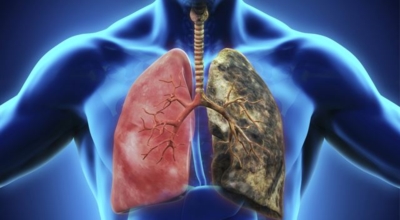

척추동물 가운데 공기호흡을 하는 동물의 호흡기관. 허파 및 폐장이라고도 하고, 구조적으로 기관지와 혈관의 집합체입니다. 폐는 산소와 이산화탄소(탄산가스)의 교환을 하는 가장 중요시되는 상기입니다. 사람에게는 좌우 1쌍이 있다고 하며, 전체적으로는 반원뿔모양인데, 흉강의 중앙을 차지하는 종격을 사이 에 두고 가슴의 좌우에 자리 잡고 있어요. 좌측의 심장으로 기인해서 오른쪽 폐가 조금 더 크다.

긴 시간의 흡연은 기도의 보호 메커니즘을 훼손시켜 기관, 기관지, 폐 간질 또는 폐에 훼손을 주어 폐 기능의 건강에 영향을 미칩니다.